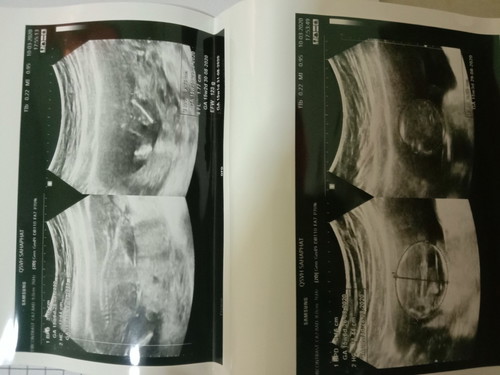

เเม่ๆช่วยดูหน่อยสิคะ ว่าเพศอะไร ทางนี้ดูไม่ออกเลยจ้าาาา

ผู้ชายรึเปล่าคะ

กำลังจะเป็นแม่